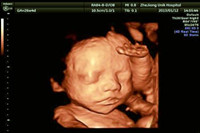

孕期里最重要的檢查就是B超檢查了,說起四維彩超的好處那真的是數(shù)不勝數(shù)。下面,就讓我們一起通過以下的,【雙胞胎四維彩超圖片】來進(jìn)行了解,文中還會(huì)告訴你,雙胞胎做四維彩超的最...

四維單子看胎兒性別的方法在網(wǎng)上瘋傳,據(jù)說單子上有M代表男寶寶,F(xiàn)就代表女寶寶。但是單子上的英文和數(shù)字非常多,很難揪出這兩個(gè)字母,讓我來告訴你四維單子上M和F在哪里...

四維彩超它是目前最先進(jìn)的彩超設(shè)備,說起四維彩超的功能和作用,相信只要是懷孕過的媽媽們一定都十分清楚,四維彩超不僅可以檢測(cè)篩查胎兒畸形,而且它還可以很全面的檢測(cè)出寶...